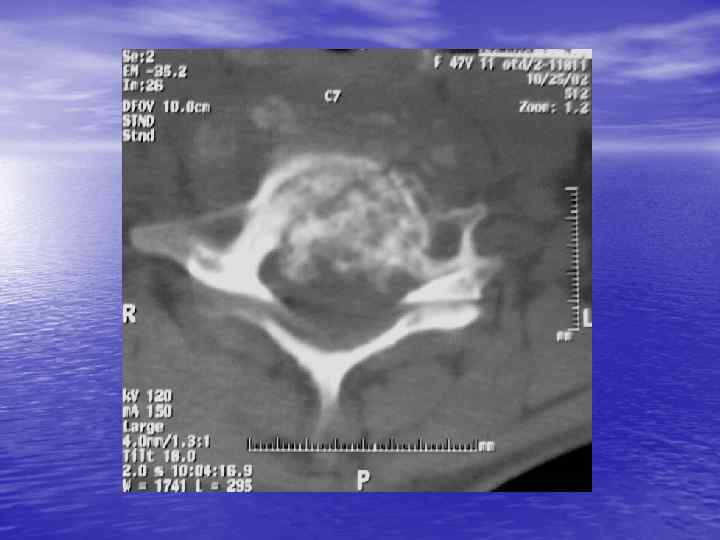

Структурный анализ Оценка основных макроскопических признаков: - положение - форма - размеры - характер контуров и структур патологически измененных участков

Структурный анализ